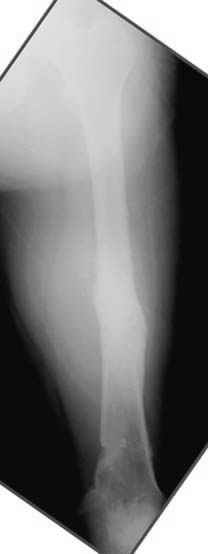

пластическая модель; и коррекция бедра аппаратом Илизарова.